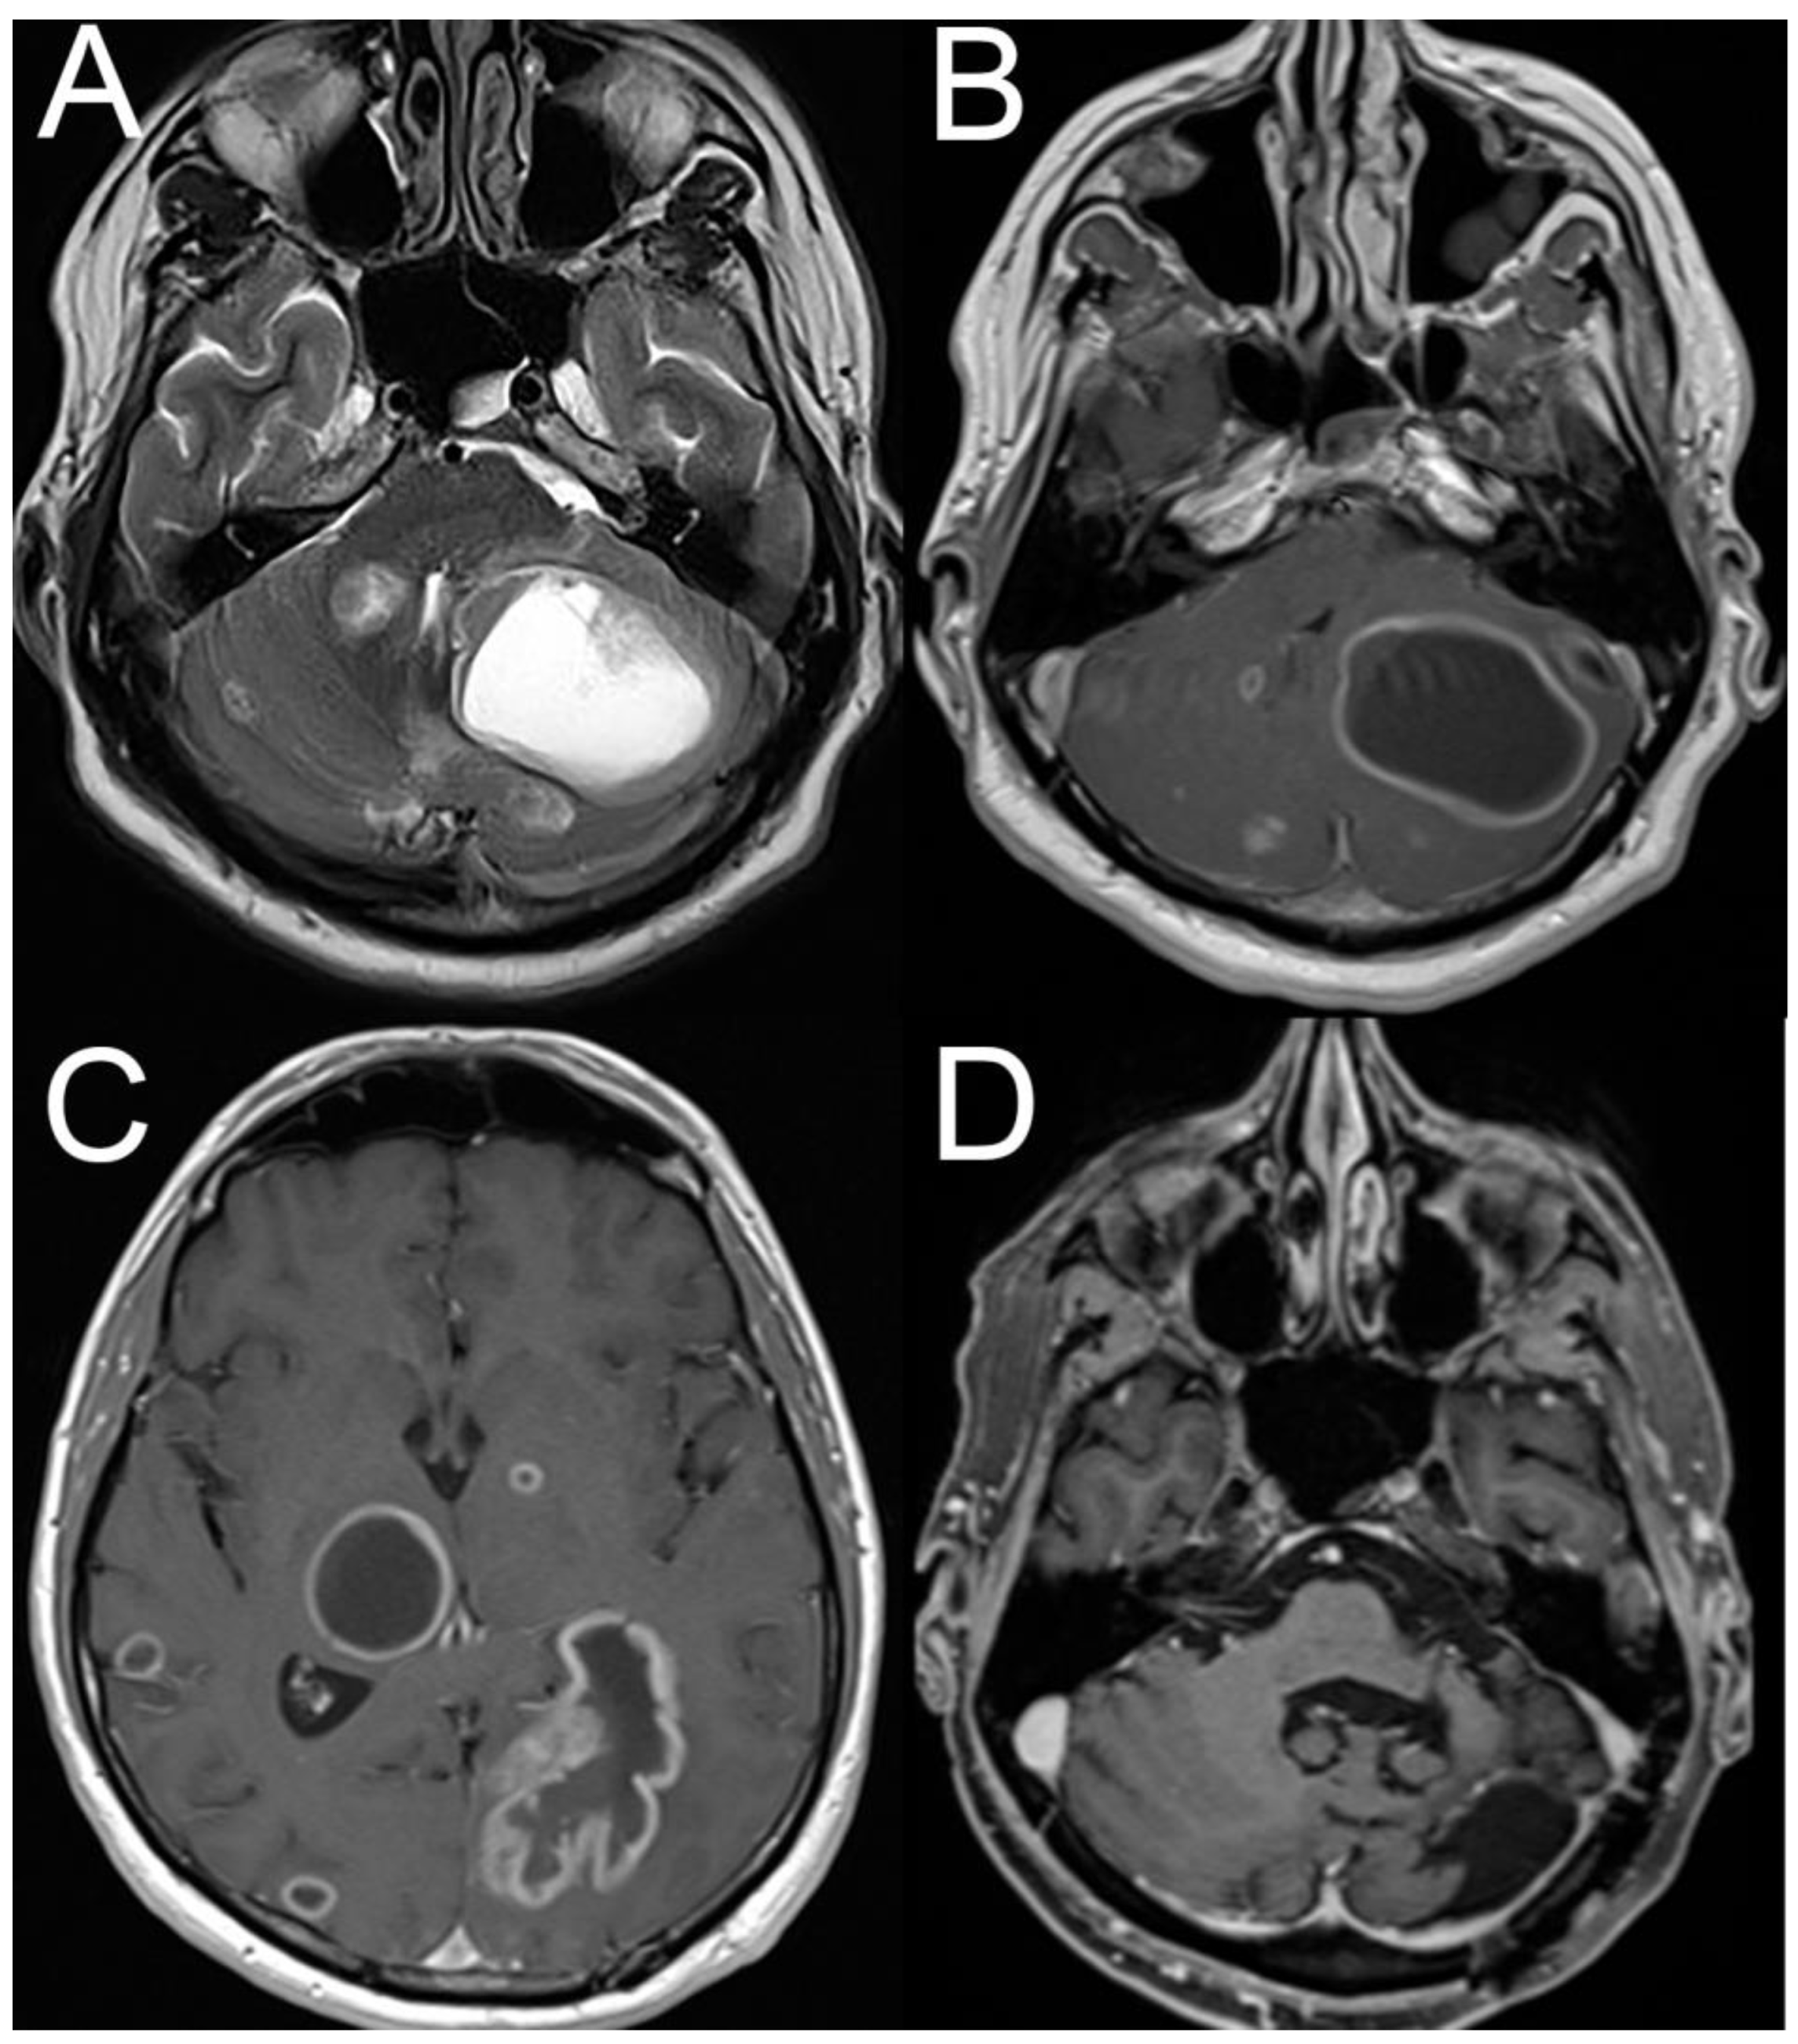

- Park, J.Y.; Kim, C.H. Vestibular Schwannoma Presenting as Acute Vertigo Mimicking Vestibular Neuritis. Case Rep. Neurol. 2022, 14, 464–468. [Google Scholar] [CrossRef] [PubMed]

- Avalos, L.N.; Morshed, R.A.; Goldschmidt, E. Hemorrhagic vestibular schwannoma: A case example of vestibular apoplexy syndrome. Illustrative case. J. Neurosurg. Case Lessons 2022, 3, 1–4. [Google Scholar] [CrossRef]

- Kapitza, S.; Pangalu, A.; Horstmann, G.A.; van Eck, A.T.; Regli, L.; Tarnutzer, A.A. Acute necrosis after Gamma Knife surgery in vestibular schwannoma leading to multiple cranial nerve palsies. J. Clin. Neurosci. 2016, 30, 141–142. [Google Scholar] [CrossRef]

- Fadul, C.; Misulis, K.E.; Wiley, R.G. Cerebellar metastases: Diagnostic and management considerations. J. Clin. Oncol. 1987, 5, 1107–1115. [Google Scholar] [CrossRef] [PubMed]

- Spiegelberg, M.; Lemos, J.; Lee, S.U.; Choi, J.Y.; Tarnutzer, A.A. Transient Response to Liberation Maneuvers in Central Positional Nystagmus Due to Cerebral Metastases Mimicking Benign Paroxysmal Positional Vertigo- A Case Report. Cerebellum 2025, 24, 96. [Google Scholar] [CrossRef]